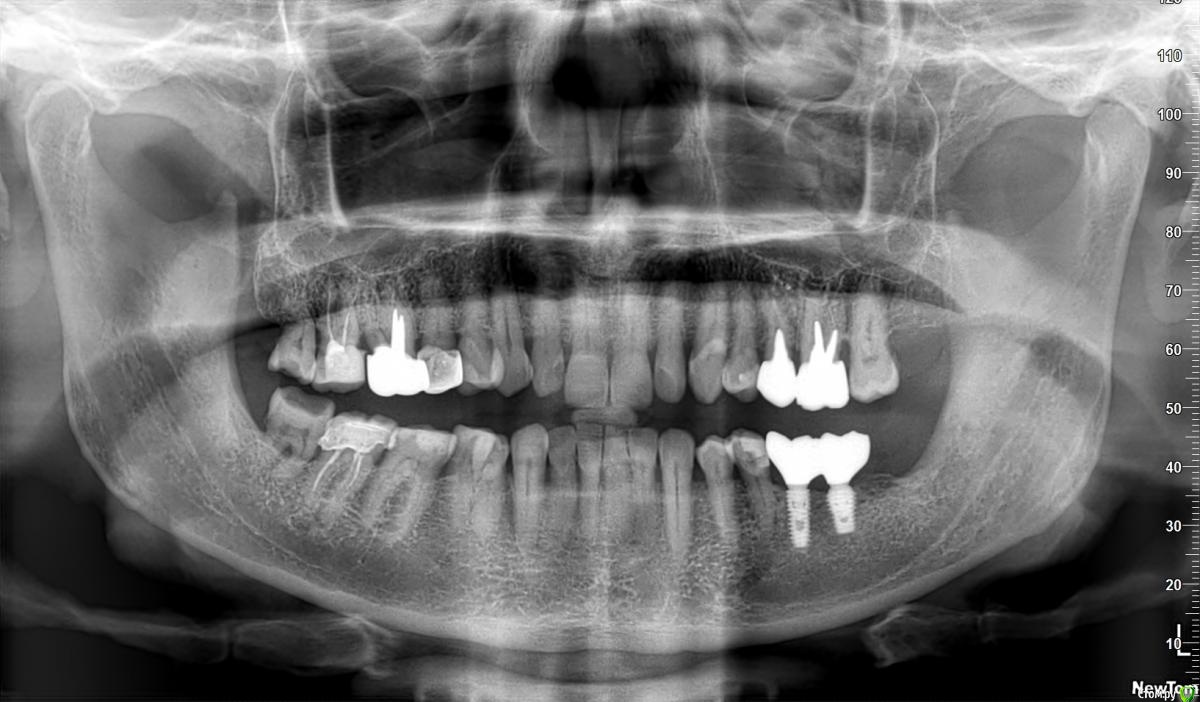

IgNat1904 Опубликовано 23 октября, 2020 Поделиться Опубликовано 23 октября, 2020 Здравствуйте, уважаемые доктора! Помогите, пожалуйста, определиться с тактикой лечения. Во время недавнего ОРВИ у меня припухла десна у 26-го зуба (раньше по его поводу врачами высказывались различные мнения). В ходе лечения общего заболевания пришлось принимать антибиотики. В результате припухлость и болезненность у этого зуба исчезла.Я сделал новую ортопантомограмму. Не могли бы вы ее прокомментировать? Есть ли зубы, которые, по вашему мнению, однозначно подлежат удалению? Если да, то как срочно это необходимо сделать?Какие зубы еще есть возможность подлечить? Буду благодарен за помощь! Ссылка на комментарий

Nazim_NV86 Опубликовано 23 октября, 2020 Поделиться Опубликовано 23 октября, 2020 Сделайте КЛКТ лучше. Судить только по ОПТГ нельзя. Сделайте скрины срезов области 25,26,47, 17 и 16. Выложите сюда. Ссылка на комментарий

Дмитрий М Опубликовано 25 октября, 2020 Поделиться Опубликовано 25 октября, 2020 Я делал КТ полгода назад, но выложить срезы технически вряд ли получится.Неужели ОПТГ в моем случае совсем не информативна?Если болит сейчас, то на КТ полугодовой давности может и не быть изменений, поэтому лучше новый ОПТГ это больше скрининговый метод диагностики (для общей картины так сказать) и это плоскостной снимок, т.е. картинка смазанная из-за наложения слоев В вашем случае на ОПТГ действительно не видно есть ли периапикальные изменения. Видно пародонтальный карман между 26 и 27 зубом, скорее всего из-за нависяющего края коронки, и да, это может вызывать болезненность и припухлость. Но обязательно нужен внешний осмотр и диагностика решение об удалении зуба(ов) не может приниматься только по снимку ОПТГ, необходим осмотр стоматолога, касаемо остальных зубов обратитесь за консультацией к стоматологу, Ссылка на комментарий